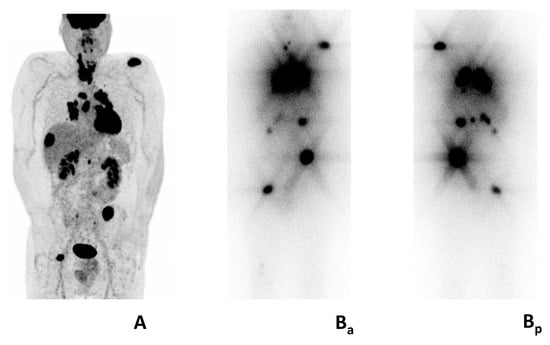

Figure 2. Mixed metabolic features in patient with metastatic follicular thyroid carcinoma. Multiple [18F]FDG avid (A) and radioiodine avid lesions (Ba, anterior; Bp posterior). Legend: male, 48 years, referred to the emergency room for intense pain corresponding to the right scapula. Multiple bone, lymph node, lung, liver, and renal metastasis at computed tomography. Bone biopsy (right scapula): follicular thyroid carcinoma. (A) preoperative [18F]FDG PET/CT: gross involvement of the thyroid gland and multiple intensely [18F]FDG-avid metastasis. Post-treatment whole body scan (Ba, anterior; Bp, posterior): intense radioiodine-avidity of most [18F]FDG-avid metastases.